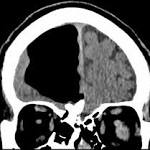

Doctors find air pocket where part of man's brain should be

3. Pocket of air found where man's brain should have been  New York Daily News